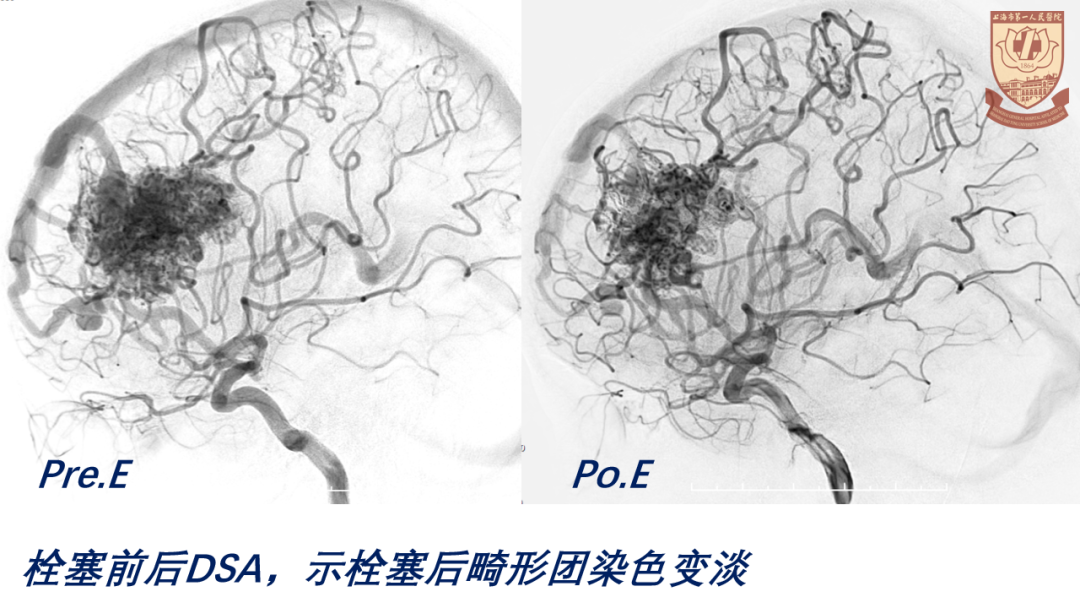

04

结果

术后GCS15分,言语正常,肢体感觉、肌力正常

脑室引流管顺利夹管、拔除

正常出院,无明显神经功能障碍

讨论

策略:

S-M分级 IV级,手术高风险;改良分级II级,可手术

综合考虑,采用部分栓塞+手术切除,一期手术